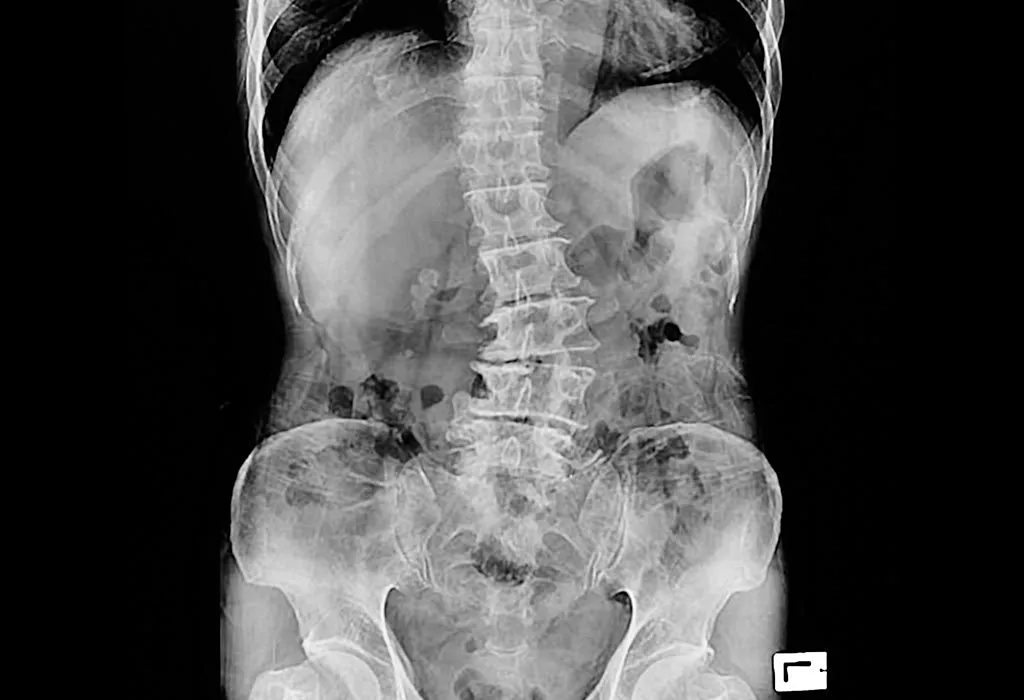

3. X-Ray

This involves taking images of various tissues, organs and bones of the body.